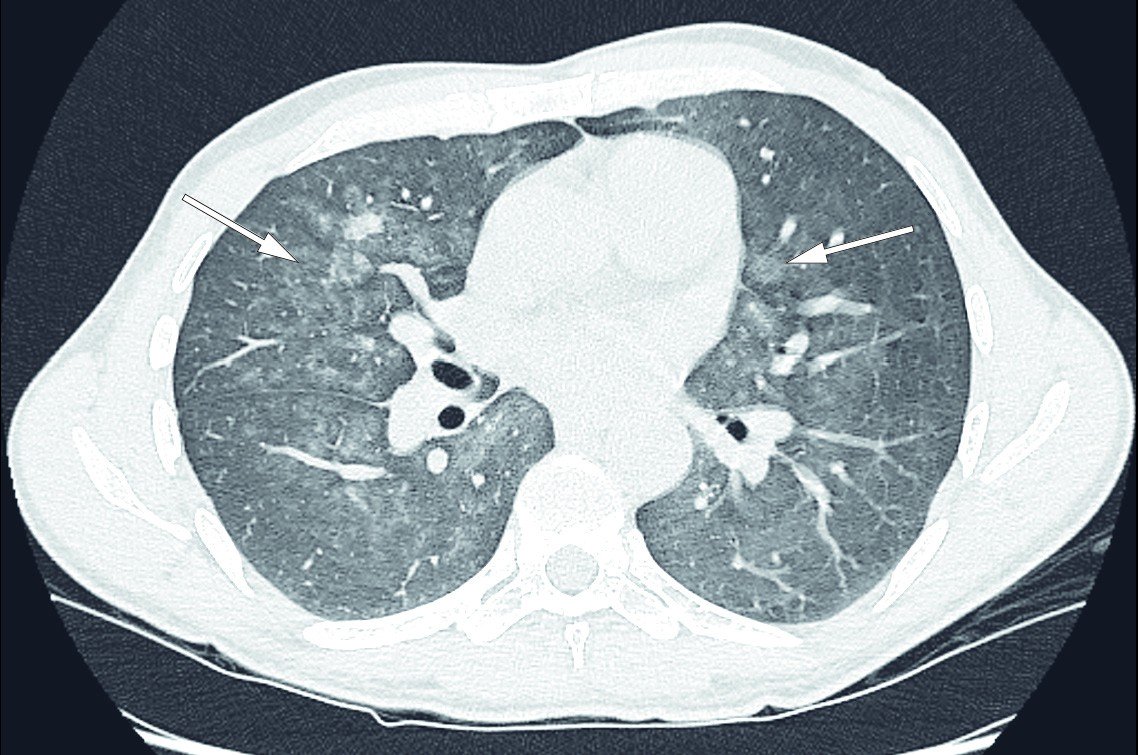

COVID-19 (coronavirus disease 2019), caused by SARS-CoV-2 (severe acute respiratory syndrome coronavirus 2), is now spreading as a pandemic. Most people will not become seriously ill, but among those needing intensive care treatment in hospital, the mortality rate is high. Massive lung affection and development of acute respiratory distress syndrome (ARDS) are characteristic of these patients. In many cases, severe systemic and local inflammation can also be observed, which may exacerbate the condition. The background for the phenomenon has not been identified, but it has been shown that SARS-CoV-2 can activate inflammasomes in the innate immune defence system, with the release of interleukin-1, by binding to angiotensin-converting enzyme 2 in the lung tissue (6). A massive release of interleukin-6 is also seen in cases of COVID-19. It is not inconceivable that a 'cytokine storm' of this type could lead to the development of secondary haemophagocytic lymphohistiocytosis with cytopenias, significant haemophagocytosis in bone marrow, and low fibrinogen concentration. High ferritin levels and persistently high CRP can give rise to suspicion that a cytokine storm forms part of the clinical picture.